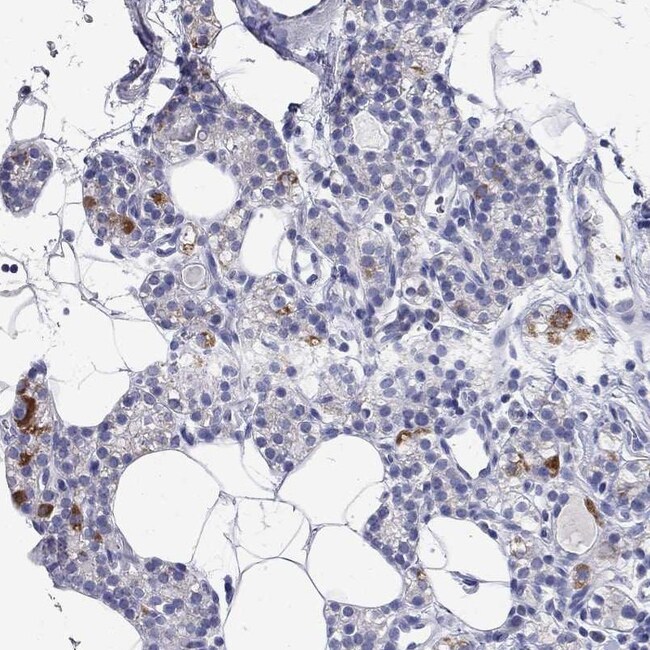

Invitrogen™ RCAN1 Polyclonal Antibody

Rabbit Polyclonal Antibody

Brand:  Invitrogen™ PA5140242

Gently mix before use. Optimal concentrations and conditions for each application should be determined by the user. Immunogen sequence: QEKEEEAEME RMRRPKPKII Q Highest antigen sequence indentity to the following orthologs: Rat - 81%, Mouse - 76%.

The RCAN1 protein interacts with calcineurin A and inhibits calcineurin-dependent signaling pathways, possibly affecting central nervous system development. This gene is located in the minimal candidate region for the Down syndrome phenotype, and is overexpressed in the brain of Down syndrome fetuses.

Immunohistochemistry (Paraffin)